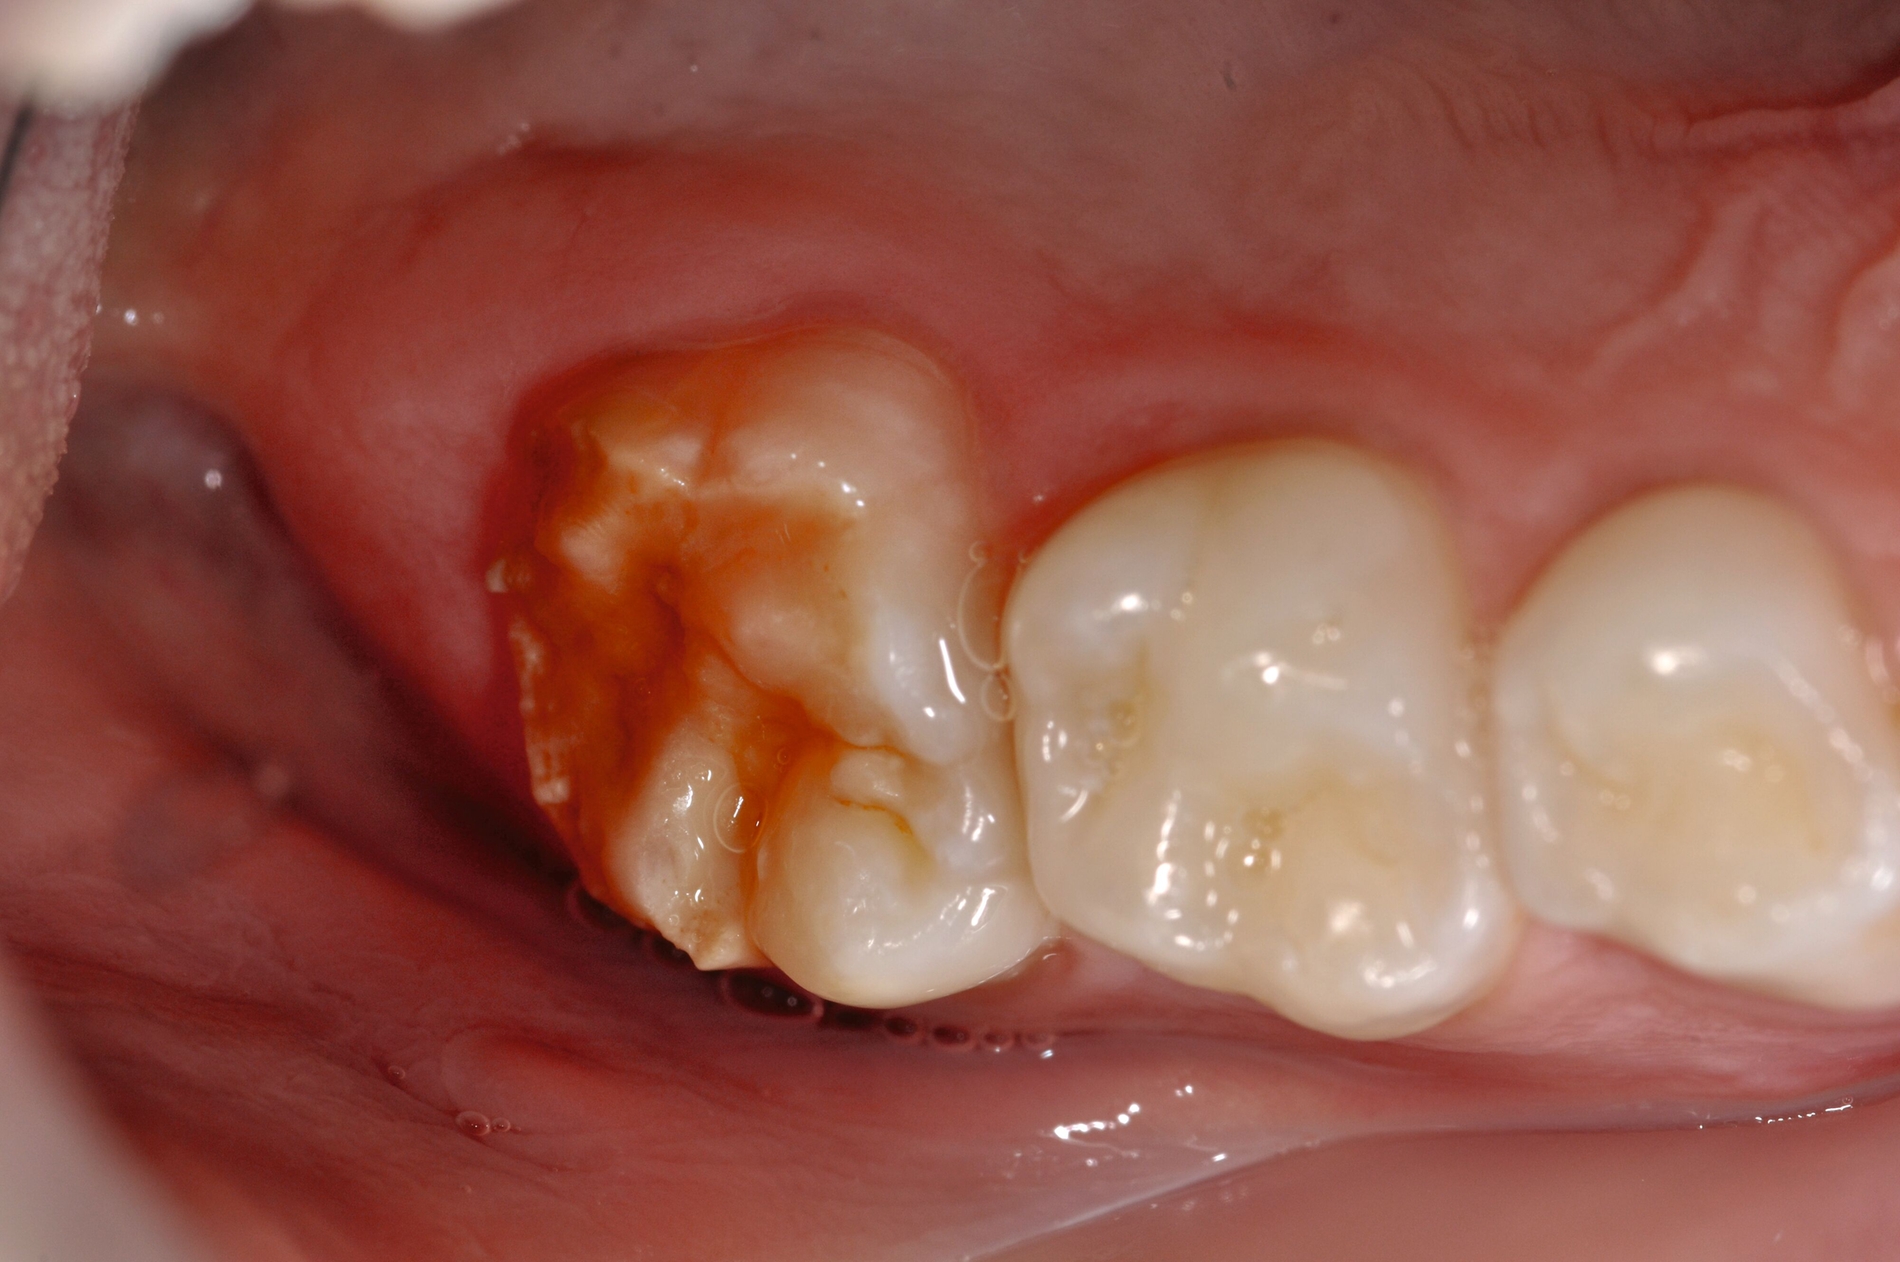

Die temporäre Therapie C (kurzfristig)

Die Therapie C hat das Ziel, MIH-Zähne vorübergehend zu versorgen, bis der vollständige Durchbruch der Zähne eine adhäsive Restauration ermöglicht, um die hypersensiblen Zähne zu desensibilisieren oder/und die Mitarbeit für die weitere Behandlung aufzubauen. Vor dem Hintergrund des erhöhten Kariesrisikos dieser Zähne (Abbildung 2) muss durch die Maßnahmen eine Kariesprogression vermieden werden.

Als mögliche Maßnahme steht eine Abdeckung der Defekte mittels konventioneller Glasionomerzemente (GIZ) zur Verfügung. Vorteil der Materialien ist die schnelle und einfache Applikation der Zemente. Bei MIH-Molaren werden diese in der Regel mittels der sogenannten ART-Technik (Atraumatic Restorative Treatment) eingesetzt [Grossi et al., 2018]. Dabei wird lediglich mit einem Handinstrument die Zahnoberfläche gereinigt und gegebenenfalls Karies exkaviert. Anschließend wird die Kavität unter relativer Trockenlegung mit dem GIZ aufgefüllt.

Der Vorteil der Methode ist, dass die betroffenen Zähne auch ohne Lokalanästhesie und Präparation versorgt werden können. Die temporäre Versorgung ermöglicht es, die Patienten an die zahnärztliche Behandlung zu gewöhnen. Häufig führt diese temporäre Versorgung auch zu einer Reduktion der Hypersensitivität der MIH-Zähne. Nachteil der GIZ-Versorgung ist das Risiko einer Füllungsfraktur oder eines vollständigen Verlusts der Füllung (Abbildung 4). Aktuelle Erhebungen bestätigen eine Erfolgsrate von über 80 Prozent nach einem bis zwei Jahren [Durmus et al., 2021; Mahfouz et al., 2025].

Der Behandlungsfall (Abbildung 4d) veranschaulicht die Schwächen des Verfahrens. Wird das Angebot der regelmäßigen Kontrollen nicht wahrgenommen, so droht bei Verlust der Füllung die Kariesprogression. In dem vorliegenden Fall konnte jedoch eine endodontische Maßnahme vermieden und durch die selektive Kariesentfernung die Zahnhartsubstanz weitestgehend erhalten werden.